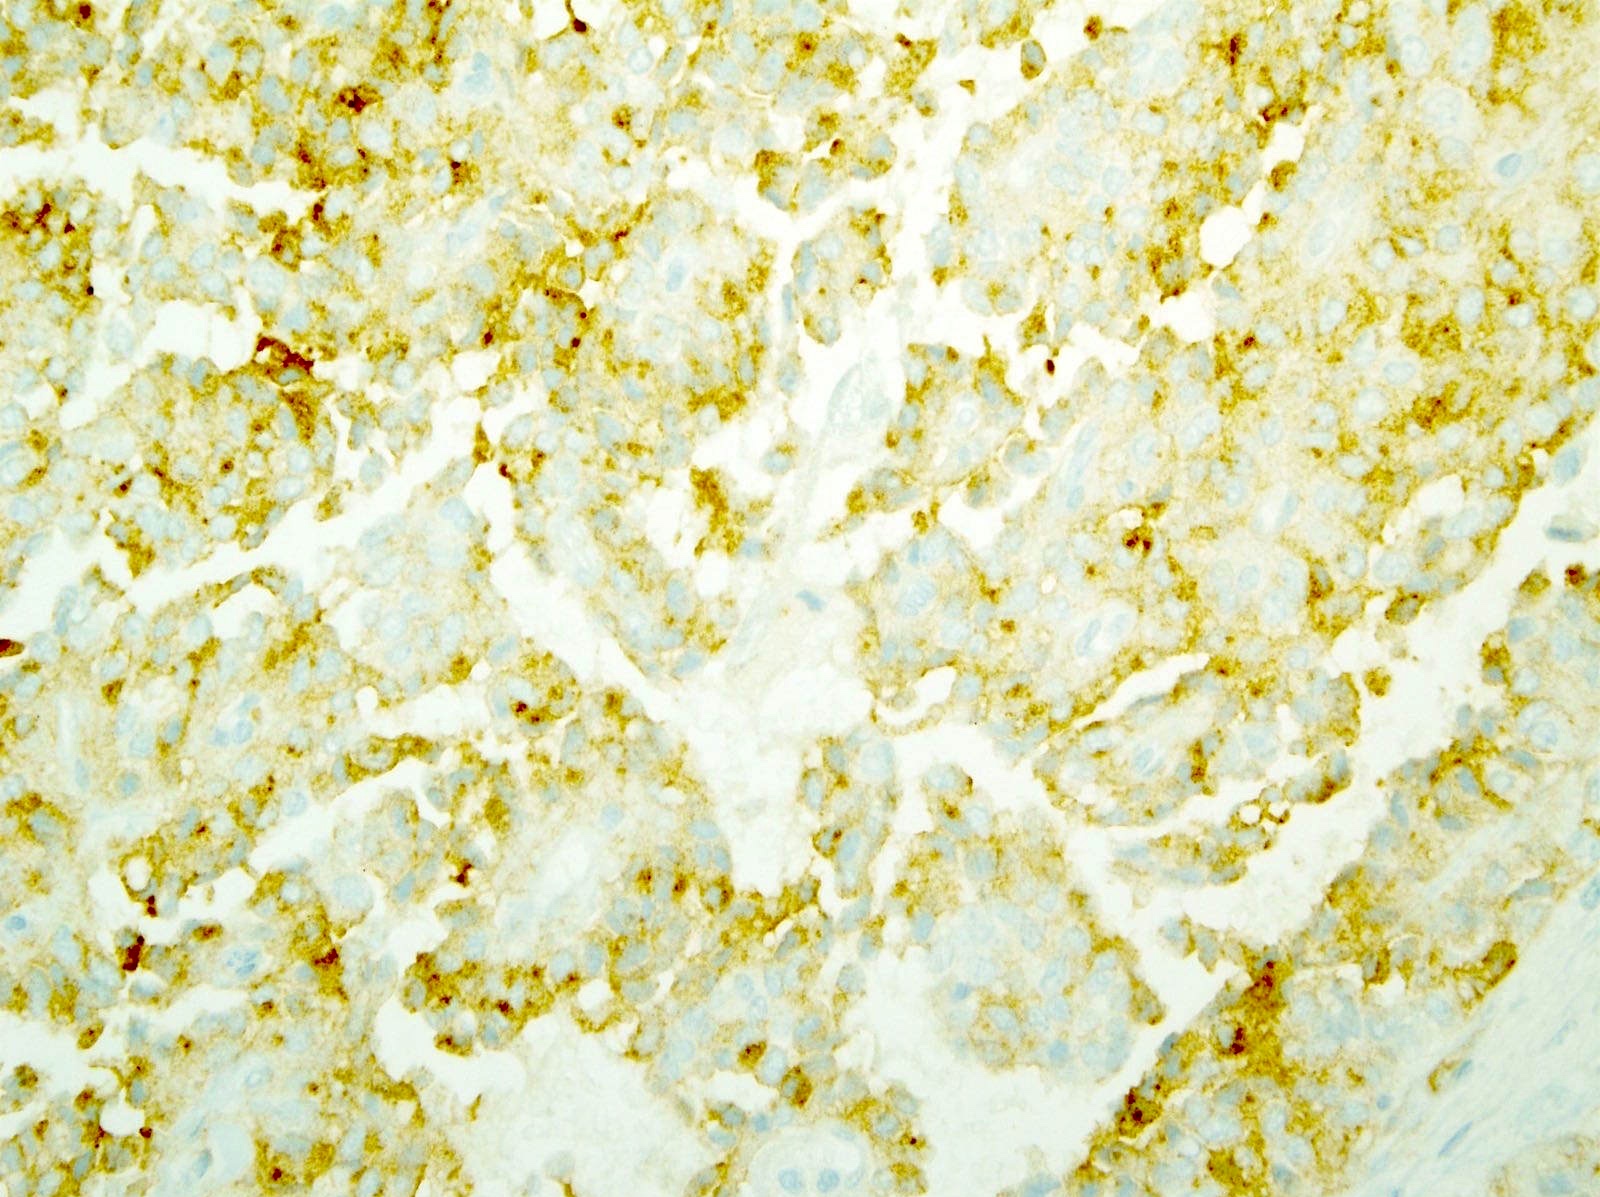

Microscopic (histologic) images

Contributed by Monika Vyas, M.D., Omid Savari, M.D. and Raul S. Gonzalez, M.D.

Positive stains

- Beta catenin (98%): aberrant nuclear expression

- E-cadherin (loss of membranous expression) (Hum Pathol 2008;39:251)

- p120 (cytoplasmic staining with loss / reduction of membranous expression) (Am J Clin Pathol 2008;130:71)

- Alpha-1-antichymotrypsin (95%), alpha-1-antitrypsin (82%)

- Vimentin (88%)

- Cyclin D1

- CD10 (63%)

- SOX11 (100%)

- Androgen receptor (81%), TFE3 (75%), LEF1 (93%), FUS (85%), progesterone receptor (63%), claudin7, claudin5 (Am J Surg Pathol 2009;33:768)

- CD56 (96%), neuron specific enolase (70%), synaptophysin (55%)

- Cytokeratin (52%)

- CD99 (dot-like) (Am J Surg Pathol 2011;35:799)